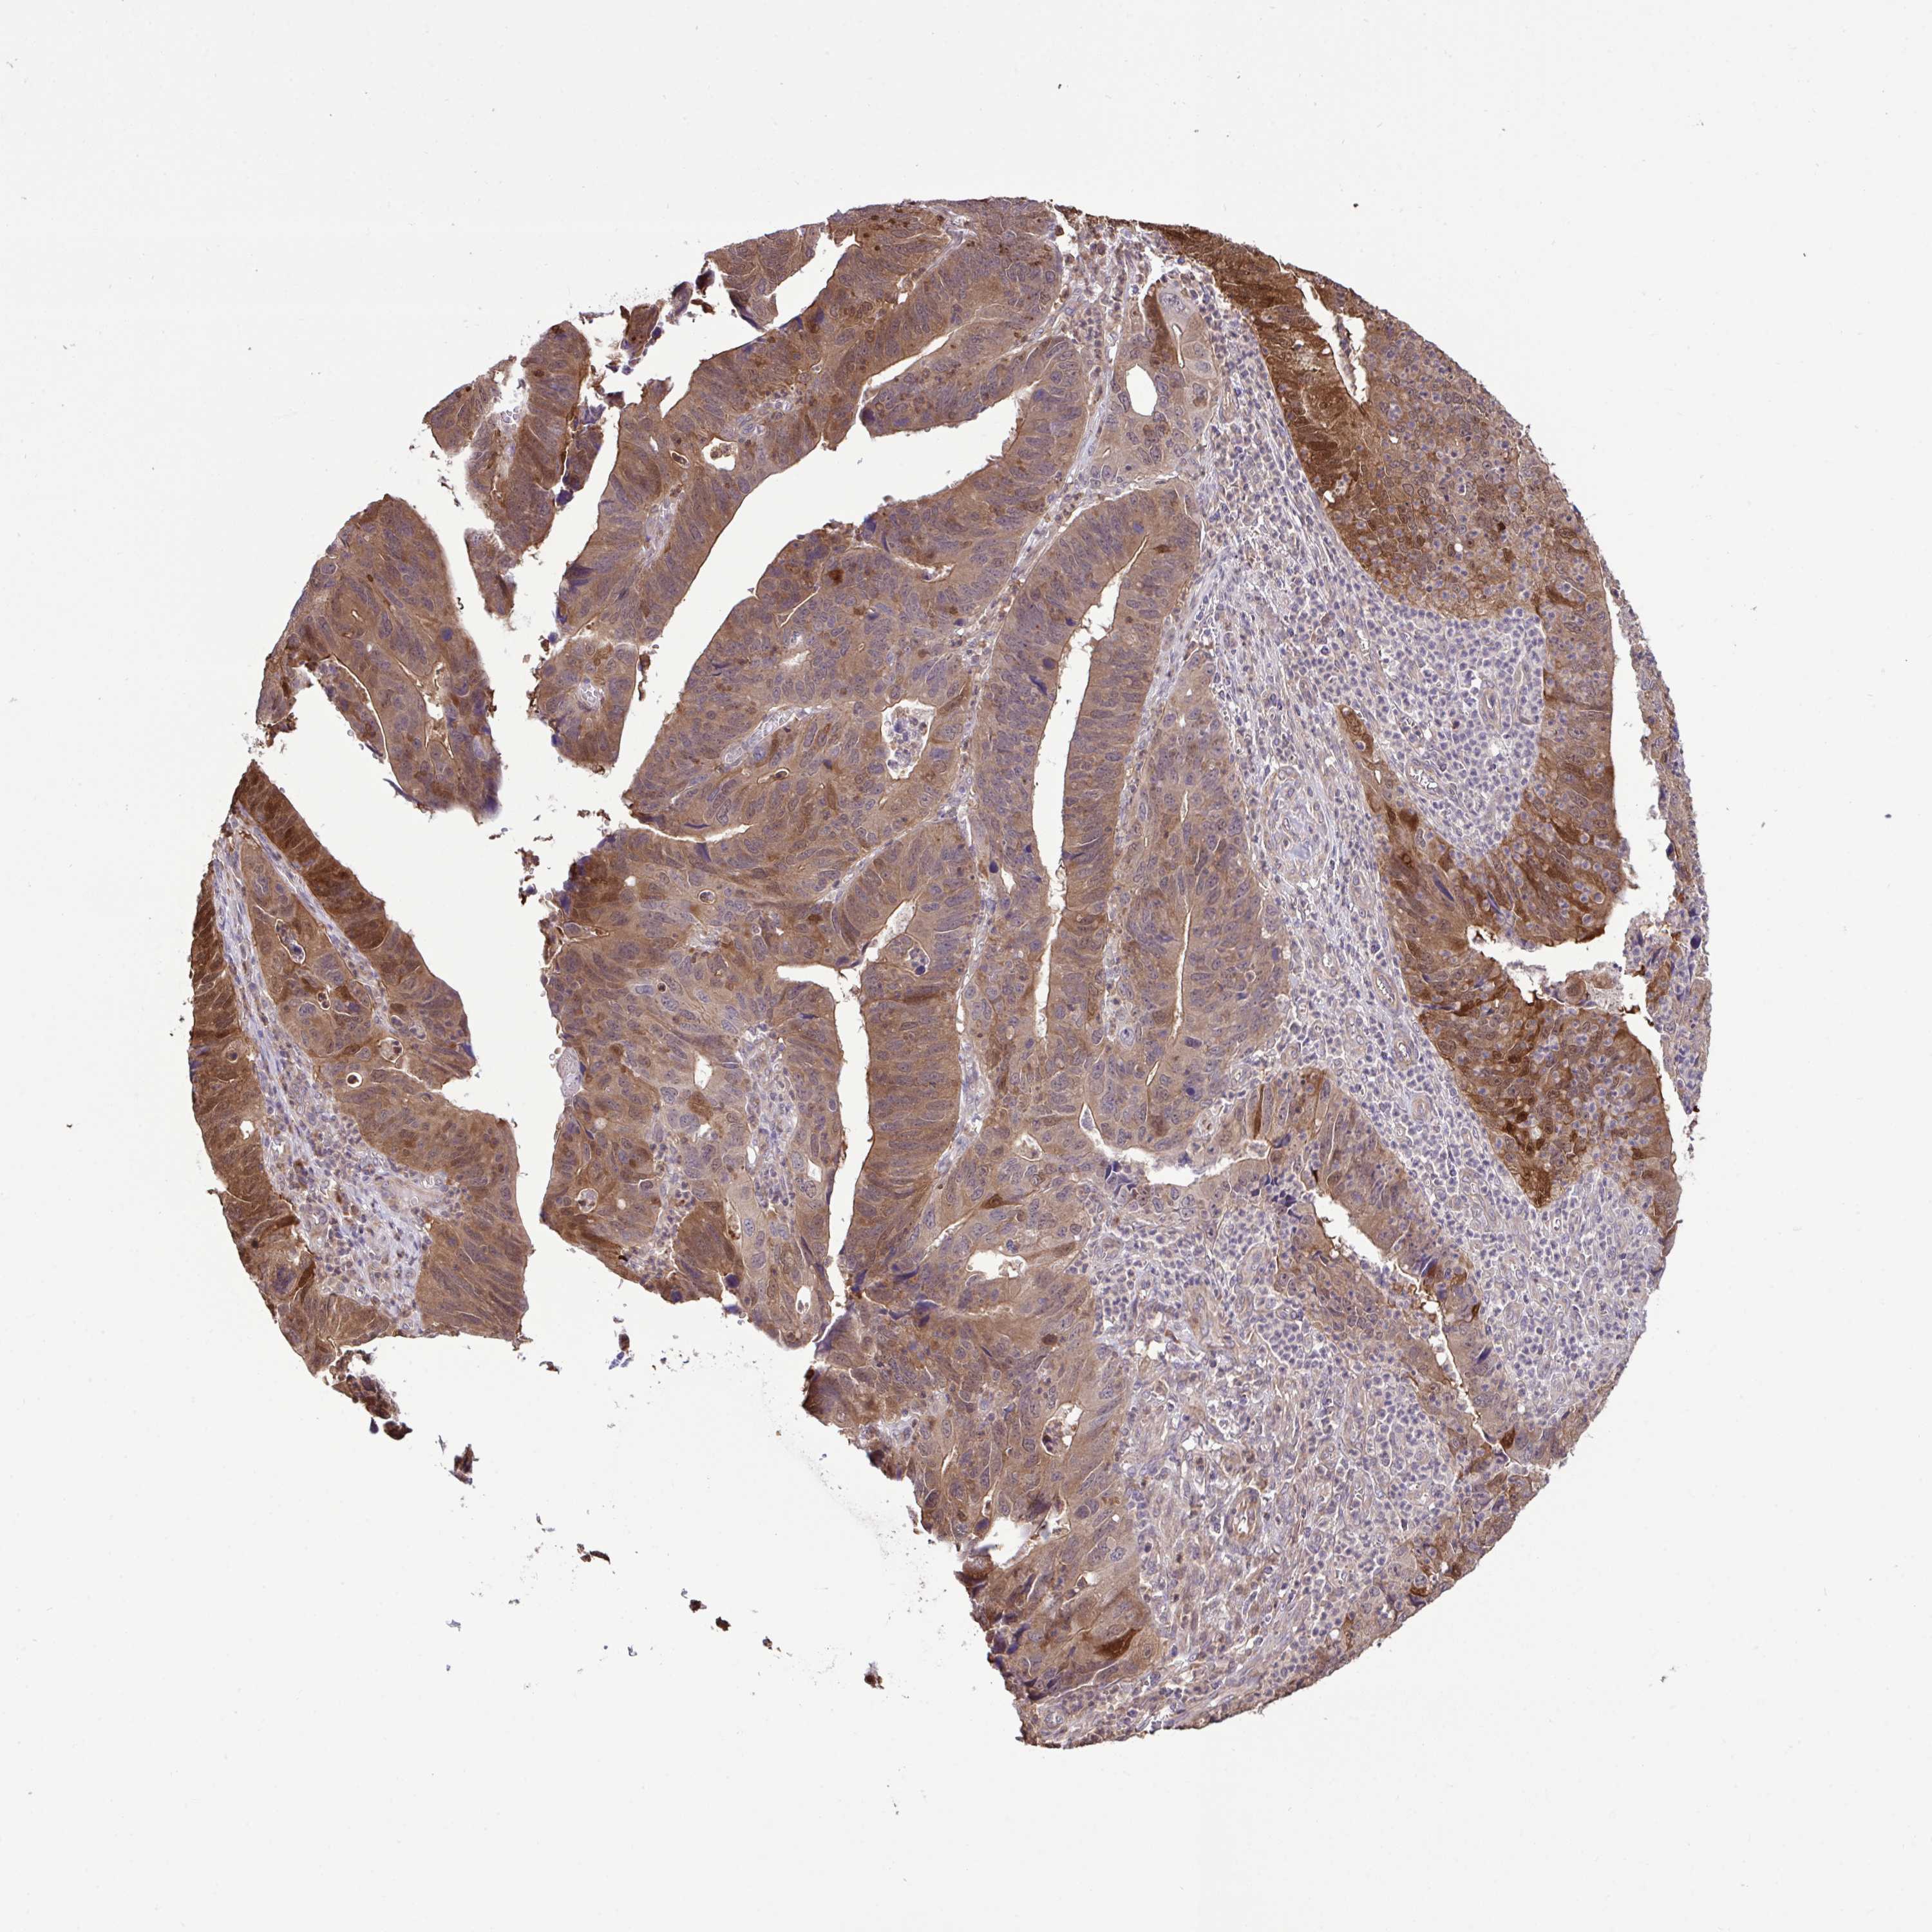

STOMACH CANCER - Protein expressioni

A mouse-over function shows sample information and annotation data. Click on an image to view it in a full screen mode. Samples can be filtered based on level of antibody staining by selecting one or several of the following categories: high, medium, low and not detected. The assay and annotation is described here.

Note that samples used for immunohistochemistry by the Human Protein Atlas do not correspond to samples in the TCGA dataset.

Antibody stainingi

Antibody staining in the annotated cell types in the current human tissue is reported as not detected, low, medium, or high, based on conventional immunohistochemistry profiling in selected tissues. This score is based on the combination of the staining intensity and fraction of stained cells.

Each image is clickable and will lead to virtual microscopy that enables deeper exploration of all samples and also displays staining intensity scores, fraction scores and subcellular localization as well as patient and tissue information for each sample.

Antibody HPA053730

Antibody HPA058604

Staining

High

Medium

Low

Not detected

Intensity

Strong

Moderate

Weak

Negative

Quantity

>75%

75%-25%

<25%

None

Location

Nuclear

Cytoplasmic/membranous

Cytoplasmic/membranous,nuclear

Adenocarcinoma, NOS